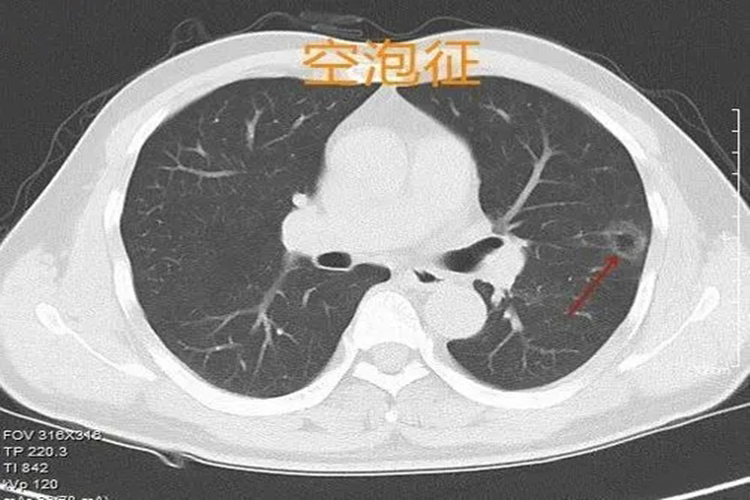

通常肺结节的密度越高则恶性概率大,密度越低则恶性概率偏低;空泡征、空气支气管征等结构常见于肺部浸润性腺癌。